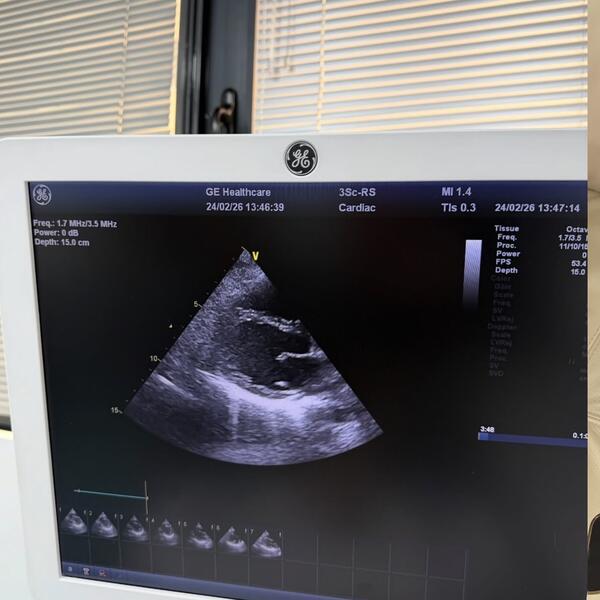

• Subakutni perikarditis: Zapaljenje srčane maramice izazvano virusom.

"Želela sam ovo da podelim kako bi moji fanovi razumeli zašto me nije bilo. Nadam se brzom oporavku i povratku karijeri koju najviše volim," napisala je ona uz fotografiju sa Holter monitoringom i aparatima za pritisak.